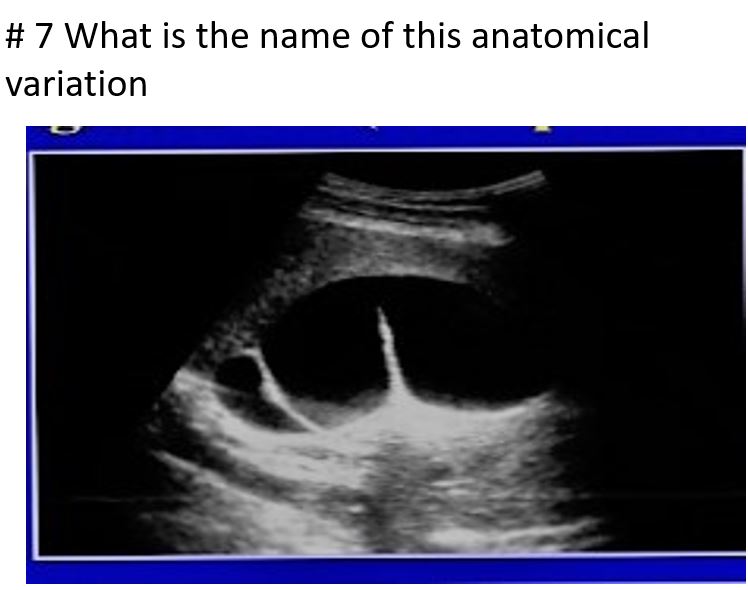

phrygian cap

sigmoid gallbladder or junctional folds